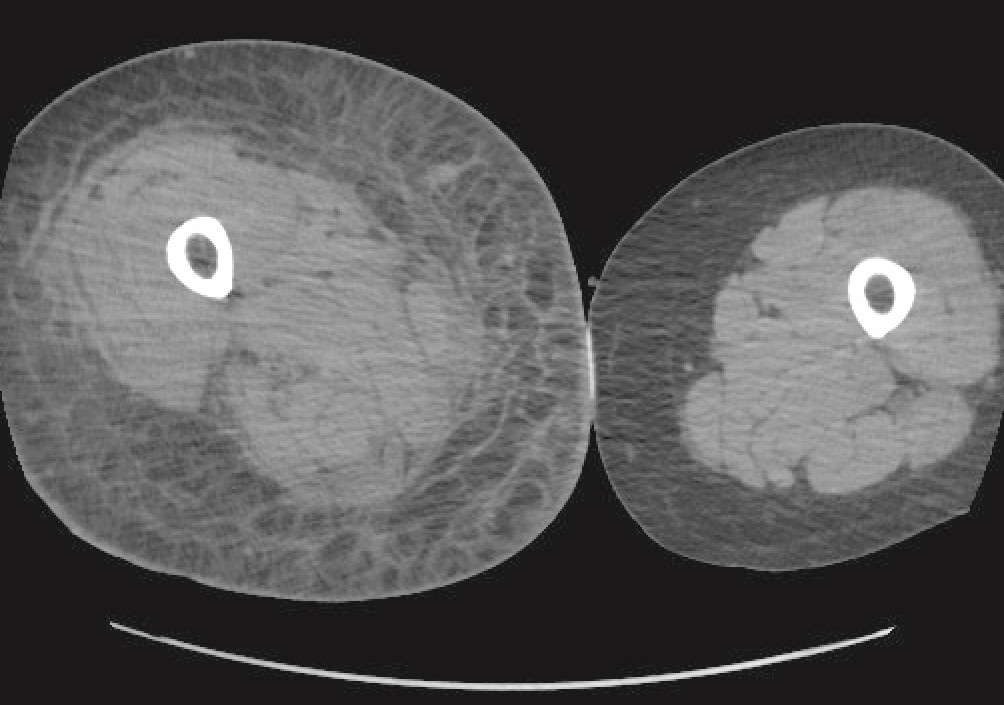

Abscess og dyp bløtdelsinfeksjon var aktuelle differensialdiagnoser på nåværende tidspunkt. Supplerende undersøkelser med CT av brystkasse, buk, bekken og underekstremiteter ble utført. Pasienten hadde fortsatt smerter i kneet, men ikke i lår eller legg, og det hadde nå tilkommet økende hevelse i høyre lår. Antibiotikaregimet ble utvidet og inkluderte nå klindamycin og piperacillin-tazobaktam.

CT av høyre underekstremitet viste nå kraftig subkutant ødem innbefattende dypere strukturer som muskel og fascie (figur 1). CT av brystkassen og buken viste flegmone i bukveggens muskulatur. Det var ikke radiologiske tegn til gassproduksjon i dypere vev. CT-funn var forenlige med dyp bløtvevsinfeksjon, slik som nekrotiserende fasciitt. Pasienten ble overflyttet til nærmeste sentralsykehus med plastikkirurgisk kompetanse etter totalt fem dager på lokalsykehuset.